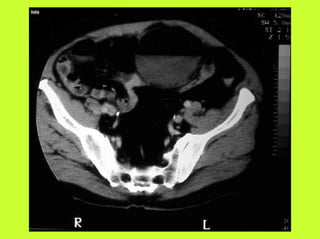

3) RADIO (PNO)

RADIOGRAPHIES

ABDOMEN SP -scanner

PNEUMOPERITOINE SUR SUJET DEBOUT

" Croissant gazeux sous diaphragmatique

" Disparition du niveau hydroaérique gastrique

PNEUMOPERITOINE SUR SUJET COUCHE

" Visibilité du ligament triangulaire du foie

" Visibilité anormale des parois intestinales

" Image aérique pré-hépatique

"Pneumatisation de MORRISSON

(cul de sac inter-hépato-rénal)

AUTRES EXAMENS

"TOGD aux hydrosolubles?

" Echo, scanner

" Coelioscopie ?

" Pas de lavement colique, pas de fibroscppie, pas de coloscopie, pas

d’IRM